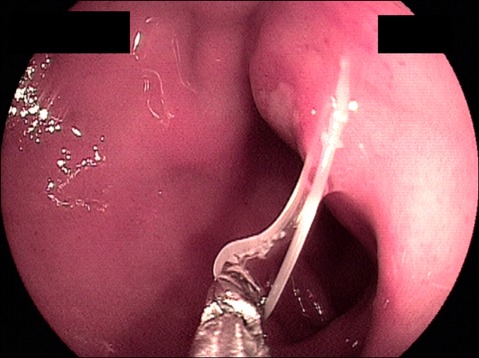

On admission, EGD revealed a round to oval active duodenal ulcer, about 10 mm in diameter, with a sharp margin and marginal elevation at the duodenal bulb. At 5 mm away from the ulcer margin, a whitish linear worm was found with half of its body penetrating the duodenal mucosa (Fig. 1). The worm was removed by using biopsy forceps (Fig. 2). Additionally, a rapid urease test showed a negative result. A proton pump inhibitor (pantoprazole 40 mg, 1 tablet qd) was administered to treat the duodenal ulcer. The patient's symptoms rapidly improved after removal of the duodenal Anisakis, and the patient was discharged on the third day after EGD.

FIG. 1.

The esophagogastroduodenoscopy at admission showed a round to oval active duodenal ulcer, about 10 mm in diameter, with sharp margins and marginal elevation at the duodenal bulb. At 5 mm away from the ulcer margin, a whitish Anisakis larva was found with half of its body penetrating the duodenal mucosa.